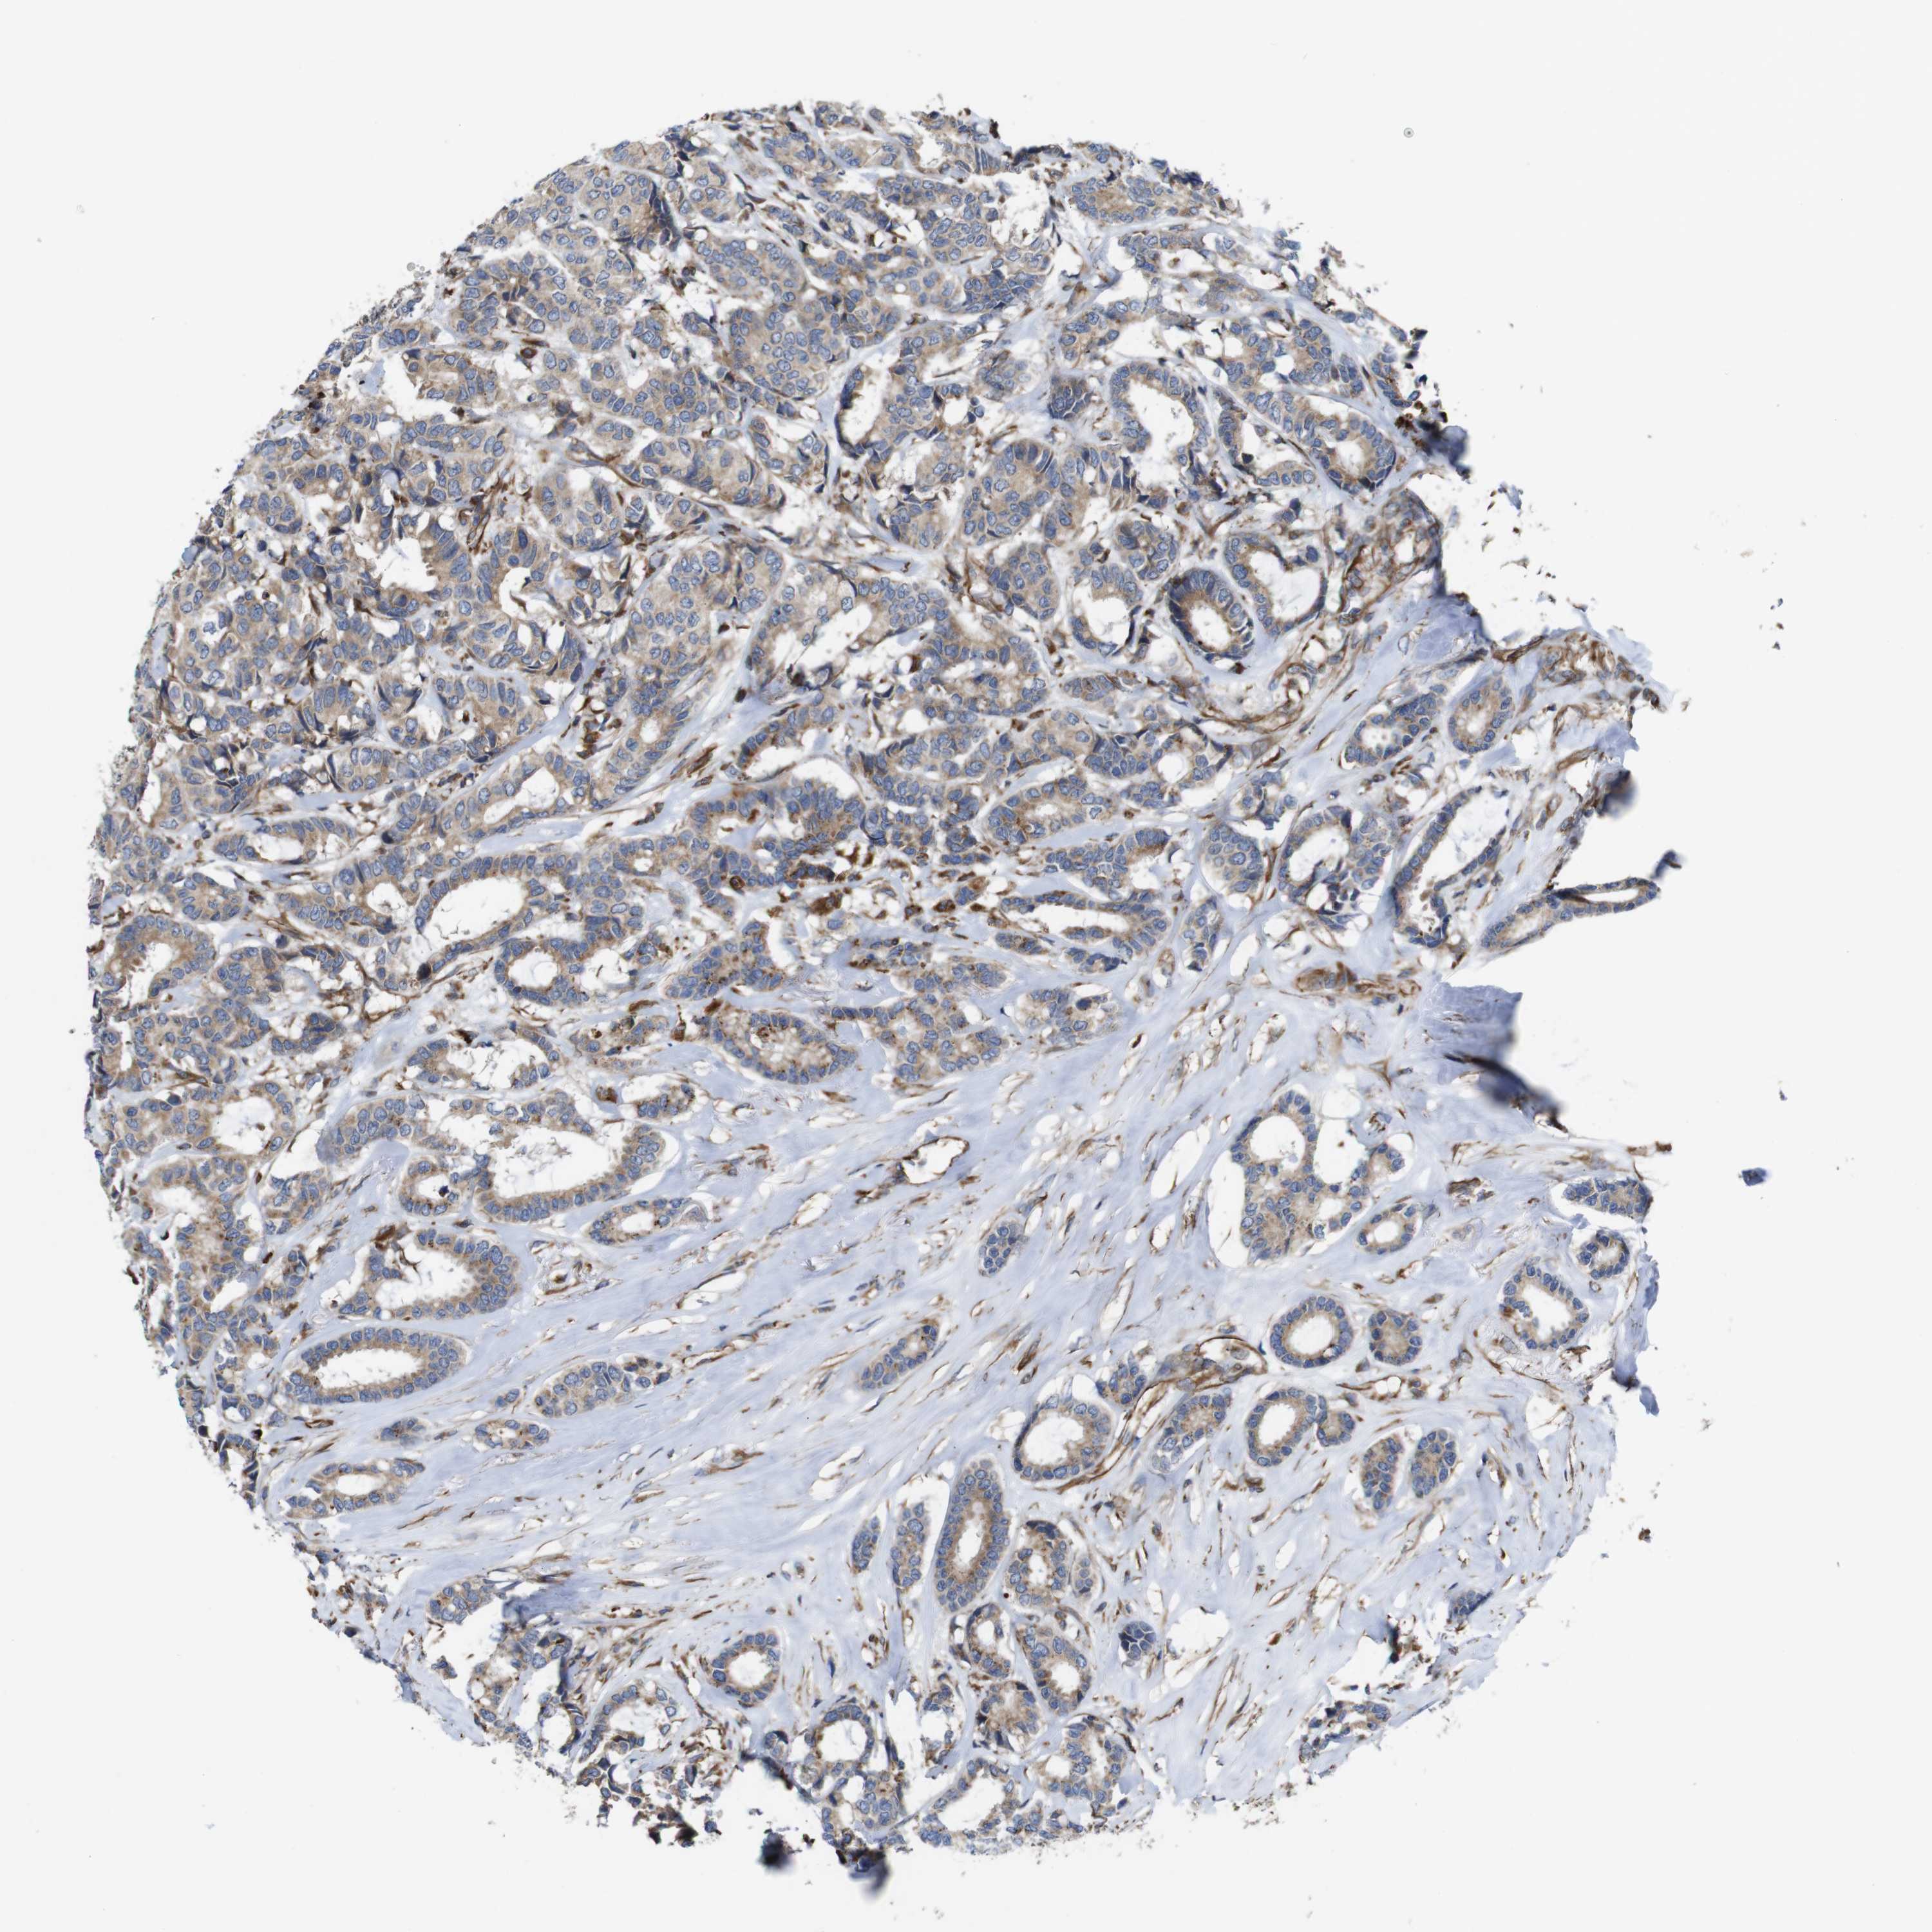

CANCER BREAST CANCER Show tissue menu

BRCA TCGA BRCA VALIDATION PROTEIN EXPRESSION